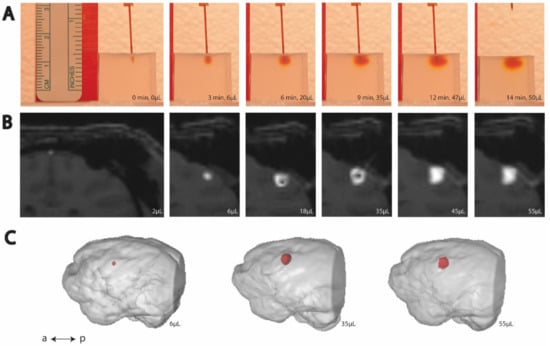

2.3. Bench-Side Modeling

2.3.2. Agar Phantom Infusion

2.3.3. Agar Phantom Image Processing